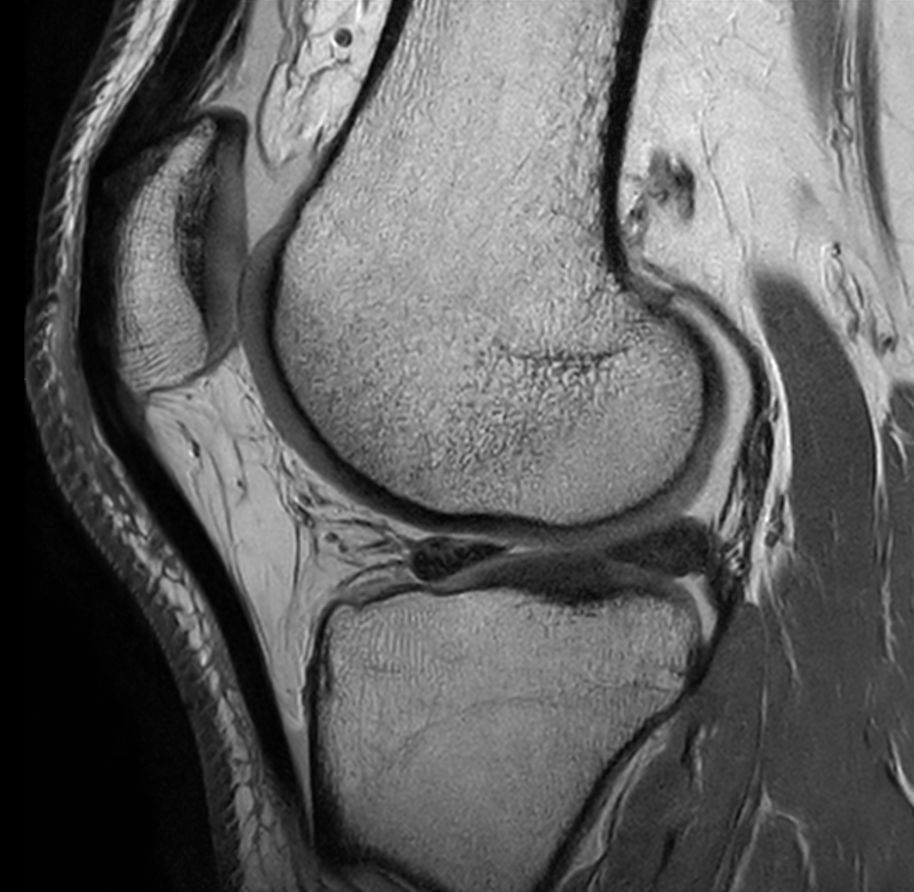

Sagittal T1w TSE - Compressed SENSE